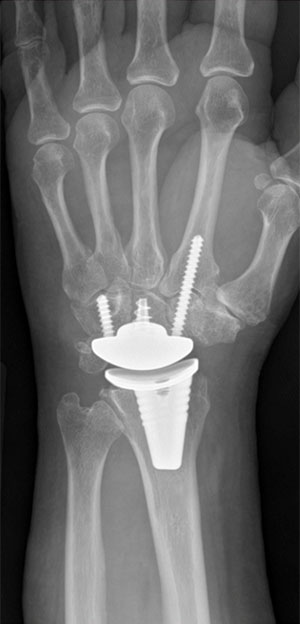

Conditions treated include TFCC tears, wrist arthritis, ganglion cysts, De Quervain’s tenosynovitis, and wrist fractures. He has a special expertise in distal radius fracture, partial and total wrist arthroplasty, and wrist arthroscopy.